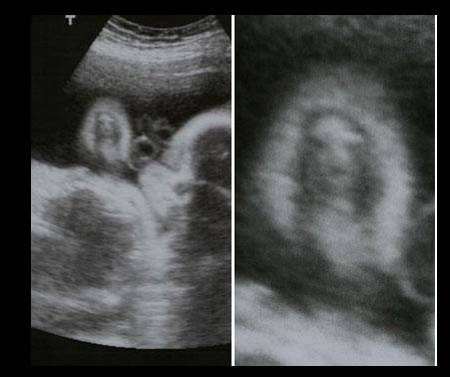

Nu mereu reușești să surprinzi atât de bine anumite imagini de ecograf. Tocmai de aceea, imaginile prezentate sunt foarte RARE!

De-a lungul timpului au fost surprinse mai multe imagini de ecograf cu adevărat uluitoare!

Iată mai jos 10 imagini de ecograf unice!